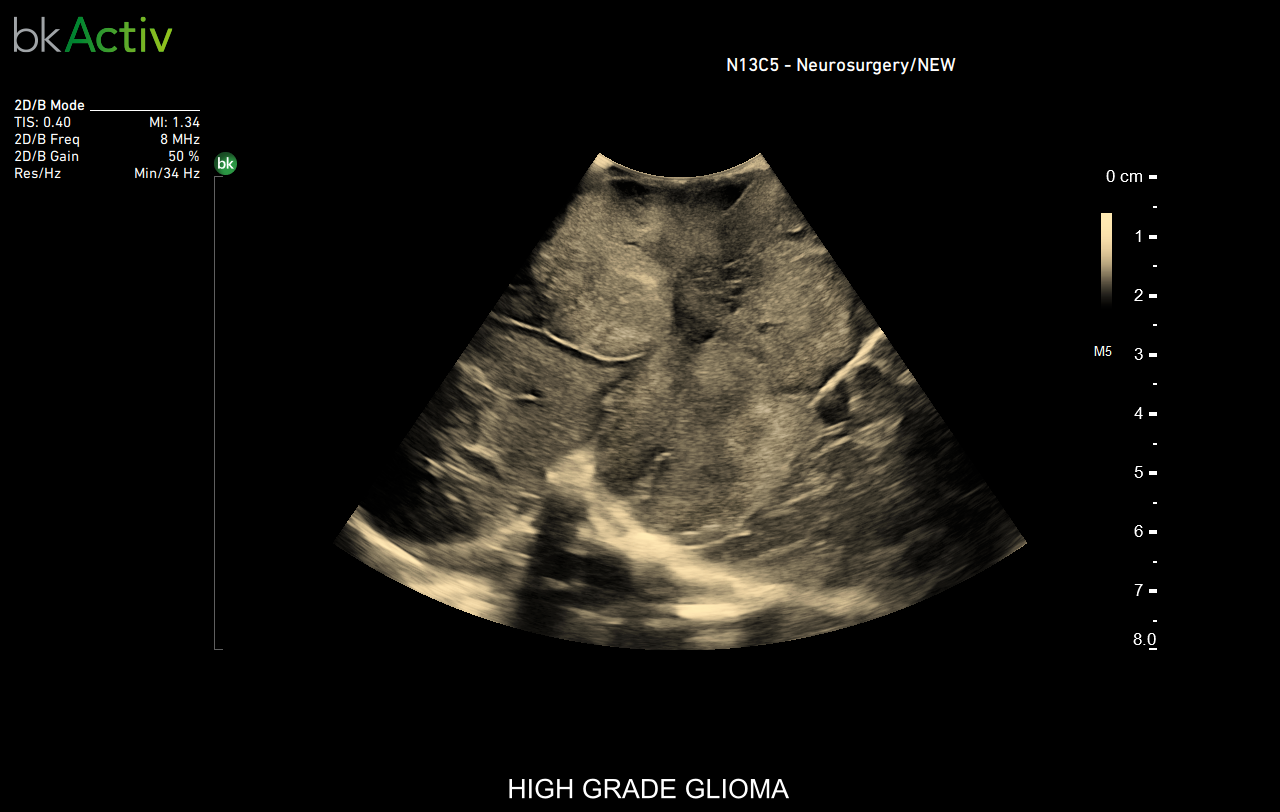

Click here to explore a recent case where the neurosurgeon used bkActiv in a glioblastoma surgery to optimize the extent of resection.